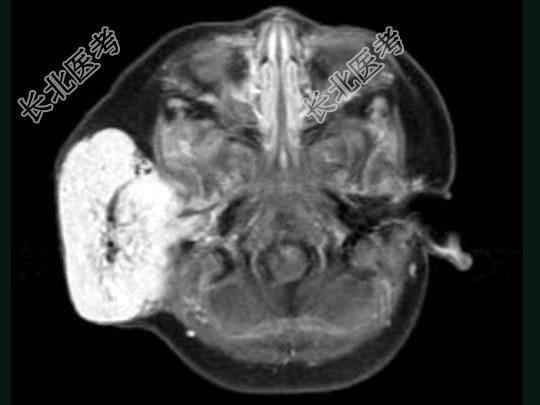

- 单项选择题老年患者,右侧面部肿胀, 呈青紫色,MRI检查如图所示, 最可能的诊断是 ( )